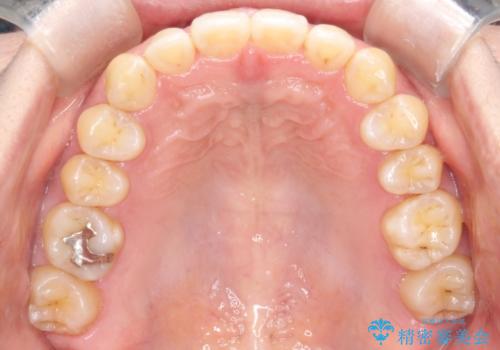

【インビザライン】前歯のすきまを閉じたい

- 前歯の隙間を主訴に来院されました。

インビザライン にて治療を行い、歯並びを改善することができました。